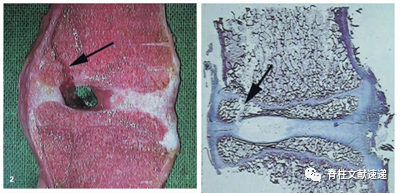

多见于青少年或青年(<35岁)腰椎间盘突出症患者;多数有较长时间的腰痛史而后才出现下肢症状;游离骨块的大小和形态与椎体的骨质缺损大致吻合,提示骨块来源于椎体。

上图所示为文献中所见大体和病理图片,可见骨骺处骨折离断。